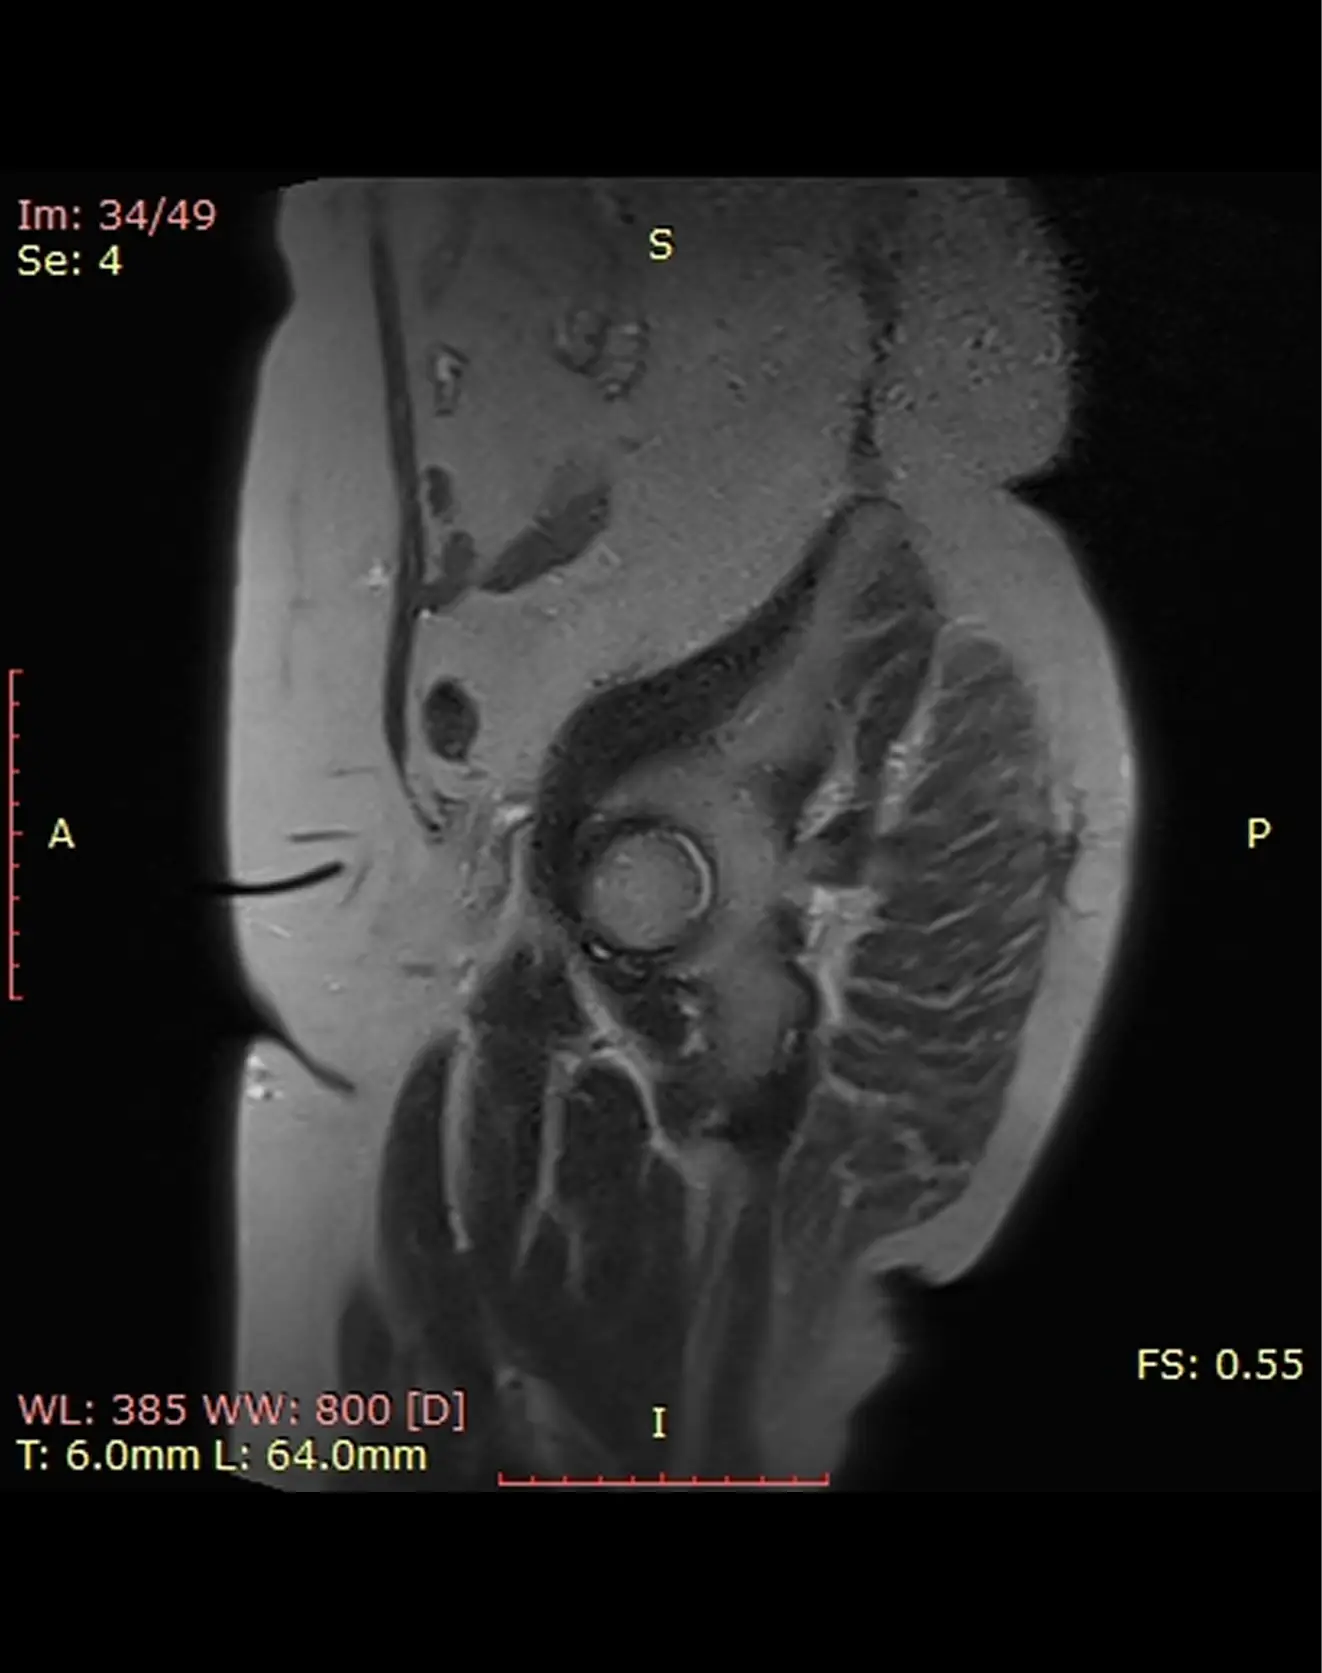

МРТ мягких тканей (любая область)